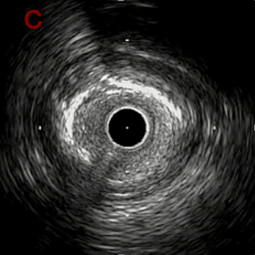

IVUS imaging after high speed 3回

a,b,cはさらに石灰化に食い込み、石灰化量は減少。

それに伴いdではbiasがさらにtentingのIVUS所見にへんかしhigh injury riskと思われた。

引き続き造影で確認してpinpointで引きのOAS high speedを3回さらに追加のためcでIVUSマーキングを行い、その点より引きで赤線のpinpoint OAS high speedを行い、dに関してはinjury回避のためにOASを当てない方針とした。